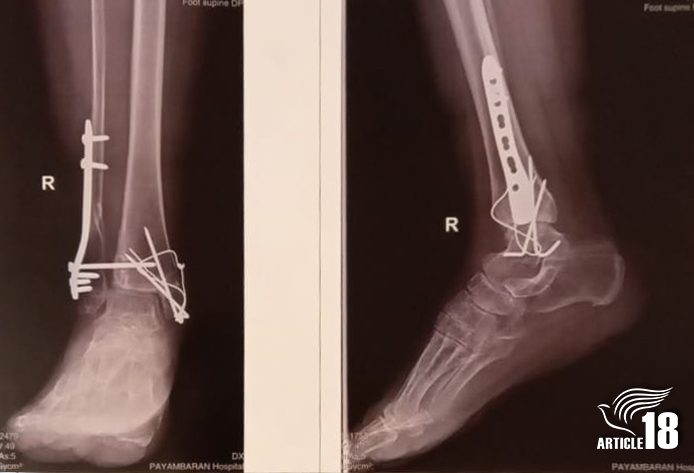

An X-ray of Mina’s leg, showing the plates fitted after surgery.

Mina’s own summons to prison was delayed after she was run over by a car, after which metal plates had to be fitted in her ankle.